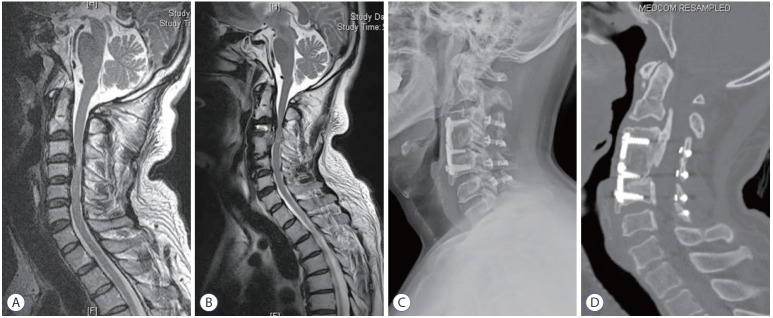

The occurrence of neurological symptoms in group PA was mainly caused by a progression of kyphosis in cervical curvature, even though there was the progression of OPLL. This mechanism differs from that of group AP, in which the majority of main OPLL lesions were removed during initial anterior surgery; progression of OPLL at a different segment led to neurological symptoms (Fig. 2). In group PA, neurological decompression had already been achieved in multiple segments during the initial posterior surgery, and progression of remnant OPLL at a different segment does not play as significant a role in development of neurological symptoms as in group AP (Fig. 3).

Fig. 2.

Case 1 (group AP). A male patient, 55 years of age, complained myelopathy including gait disturbance and clumsy hand due to OPLL of C3–5. The symptoms were recovered completely after anterior cervical corpectomy and fusion on C3–5 with corpectomy of C4 (A). He presented of newly developed myelopathy originating from OPLL of C2–3 after 65.5 months (B). Laminoplasty on C3–6 with partial laminectomy of lower C2 was performed, the newly developed symptom disappeared with remaining mild shoulder pain (C and D). OPLL : ossification of the posterior longitudinal ligament.